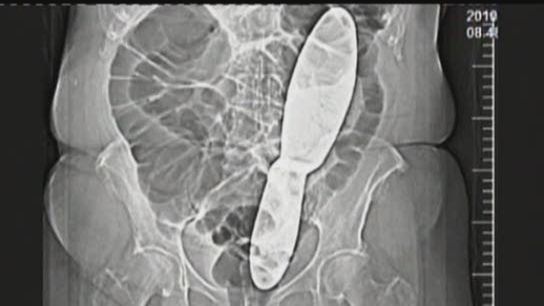

Zdenka Kopeckova po wyjściu ze szpitala nie była w stanie funkcjonować. Ból był tak silny, że chciała nawet popełnić samobójstwo. W końcu namówiła lekarzy do wykonania prześwietlenia. Okazało się, że w trakcie operacji, z powodu niechlujstwa personelu medycznego w jej ciele pozostawiono mierzące 30 cm narzędzie chirurgiczne. Pacjentka domaga się odszkodowania.